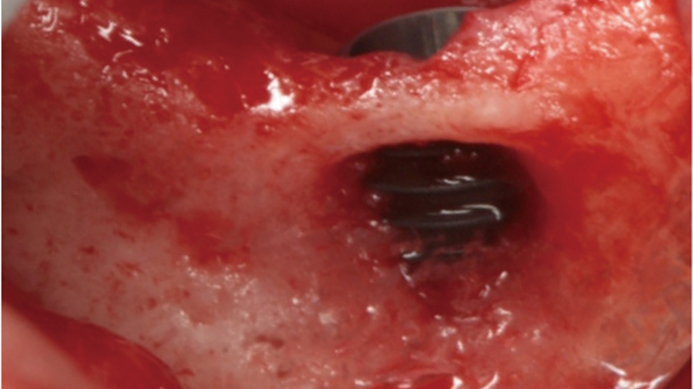

Klinikinis atvejis: Vėlyvoji implantacija: viršutinio žandikaulio ančio dugno elevacija, implanto sriegimas ir kraštinė kaulo regeneracija;

- Dr. Irfan Abas klinikinis atvejis -

Raktažodžiai:

Vėlyvoji implantacija, ančio dugno elevacija, ančio dugno elevacija atviru būdu, kraštinė kaulo regeneracija, Dr. Irfan Abas, AnyRidge, MiLA chirurginis rinkinys, kaulo regeneracija;

Produktai:

AnyRidge implantų sistema, MILA chirurginis rinkinys;